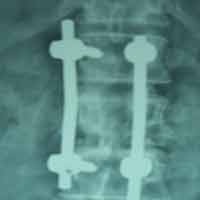

Case:2 Traumatic Fracture L2 with Cauda Equina

Male 65 years of age presented with 1 month old fracture L2 with paraparesis & bladder, bowel involvement. He was treated with Laminectomy (Decompression) & fixation with pedicular screws neurological full recovery by 10 days post-operative.

Post-op Lateral